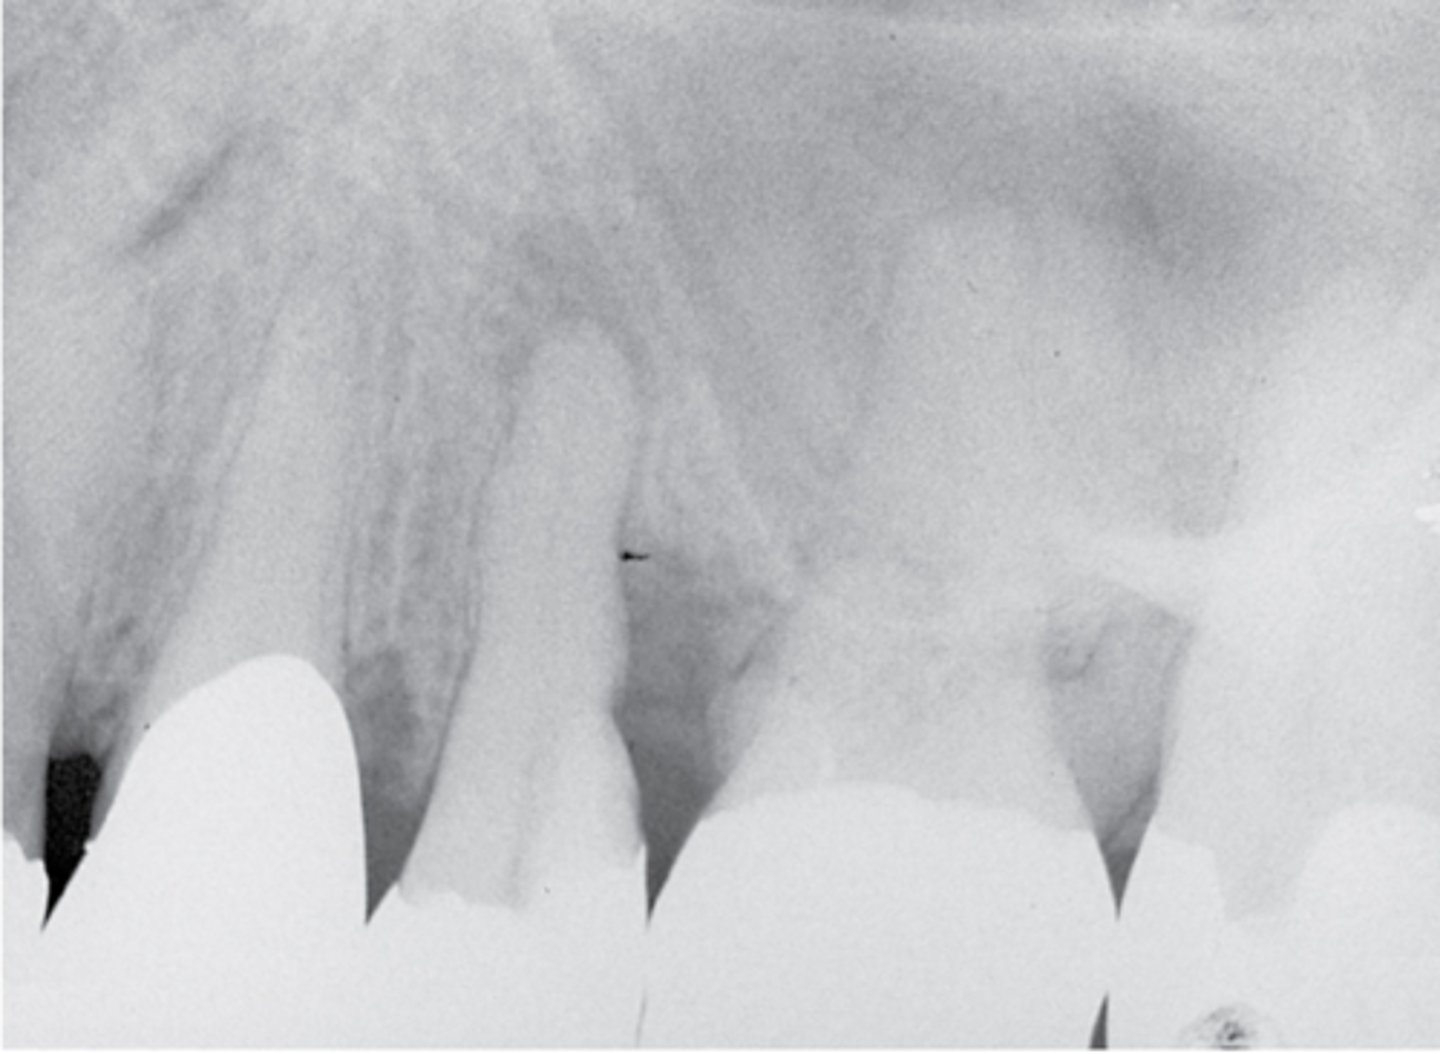

What type of lesion?

- No response to cold

- No pain on percussion or palpation

- Distal bone loss and deep pocket (independent of the PARL)

- Pulpal dx: Necrotic pulp

- Periapical dx: Asymptomatic apical periodontitis

Concomitant lesion